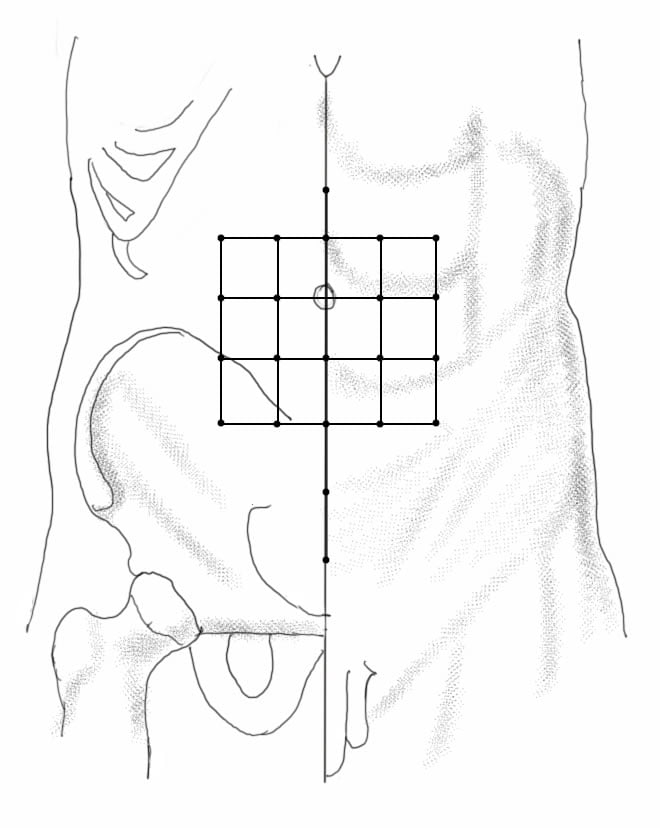

מיקום

23 נקודות.

שתי נקודות מעל הטבור, נקודה ראשונה 1 צון מעל והשניה עוד צון מעל הראשונה.

5 נקודות מתחת לטבור בהפרשים של צון.

1 צון לטרלית לנקודה הראשונה שנמצאת מעל הטבור ,3 נקודות מתחת בהפרש של 1 צון משני הצדדים ועוד 4 נקודות 1 צון לטרלית באותו הגובה בשני הצדדים.

לא דוקרים את כל 23 הנקודות אלא רק במצבים חמורים, לרוב משתמשים ב-4 הנקודות הנמצאות מעל, מתחת ובצד של הטבור.